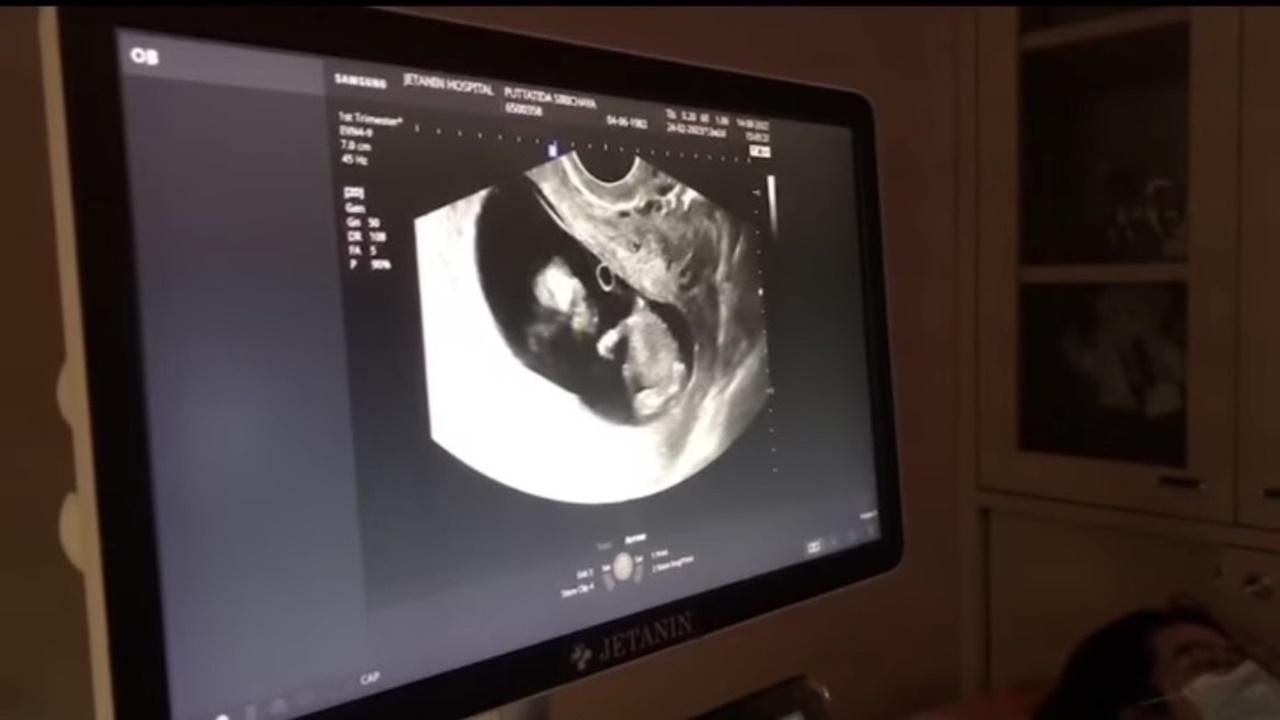

ด้วยการโพสต์คลิปอัลตร้าซาวนด์ และเขียนแคปชั่นว่า "ของขวัญวันเกิดยายและทุกคนในครอบครัวปีนี้ หลานของยาย ลูกของพ่อแม่ และน้องของมีบุญ #ตามสัญญานะคะพ่อ #คิดถึงที่สุด"